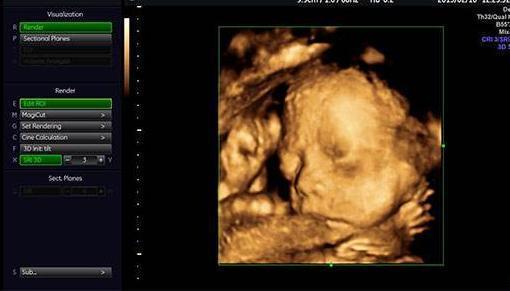

朋友28周的时候叫我陪着去体检,给宝宝照下四维彩照,看看胎儿生长发育过程中有没有变畸形。

因为宝宝在子宫内发育的非常好,活蹦乱跳的。半个小时,朋友拿着四维彩照的照片一言难尽。

这也太丑了吧!朋友说自己和老公的长相都不差,为什么生育的孩子确实塌鼻梁、大鼻孔、厚嘴唇呢?

那山根宽的像座独木桥,整个一阿凡达!欲哭无泪的朋友觉得打击太大,连着好几天都沉浸在悲伤中不能自拔。

真的是这样吗?专家解答说,其实四维彩照出来的成像与宝宝出生后的模样会有一定出入,以下三张图片告诉你。

胎儿的面部脂肪还没有完全堆积,因此从四维看到的脸蛋来说是比较丑的,类似于外星人。头部和身体的占比例大概是2:1,以成年人的视觉来看可不是怪异么。

再者,孕妇拍摄四维的目的,便是排除胎儿面部是否畸形。所以会根据声波成像技术来填充图像,再将口、鼻、眼等细节放大。

但是小宝宝的口耳鼻实在太细节,声波反弹较弱,因此连接到电脑上后会另外填充成像。毕竟四维彩照和我们平时拍照的像素不一样,它是由彩超探头采集到的数据以此合成一个大致的影像。

那么打印出来后自然模糊,边缘不清晰,导致小宝宝的五官和肢体看起来扭曲变形。一定程度上丑化了宝宝,让新手爸妈们怀疑人生。

所以,在探头勘测超声波影像时,胎儿在动。加上胎儿整个是泡在羊水里面,左动一下,右动一下,拍摄出来的成像难免会失真。

综上所述,四维彩照出来的胎儿成像,并不会是宝宝实际出生的样子。就和我们去一个餐厅吃饭一样,实物与图片不符。